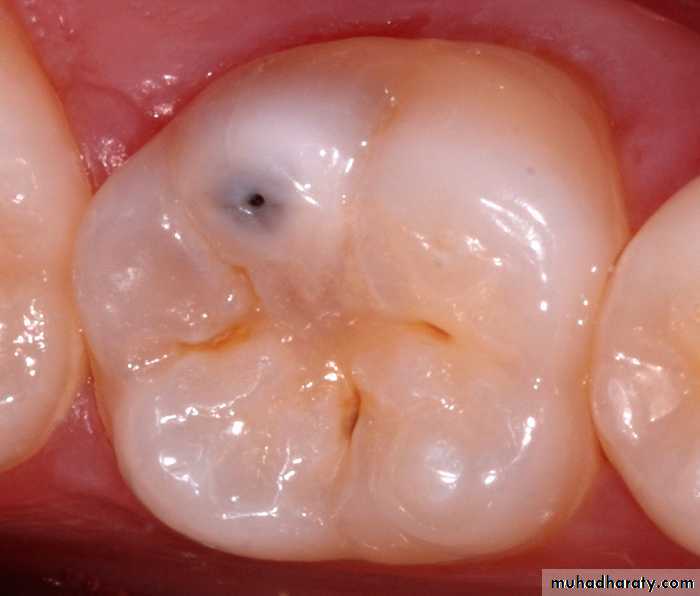

Non-cavitated carious lesion

ENAMELDENTIN

Cavitated Lesions

Where there is visual breakdown of a tooth surface, it is classified as cavitated carious lesion. An active cavity on a smooth surface has soft walls or floors as shown below:Secondary caries